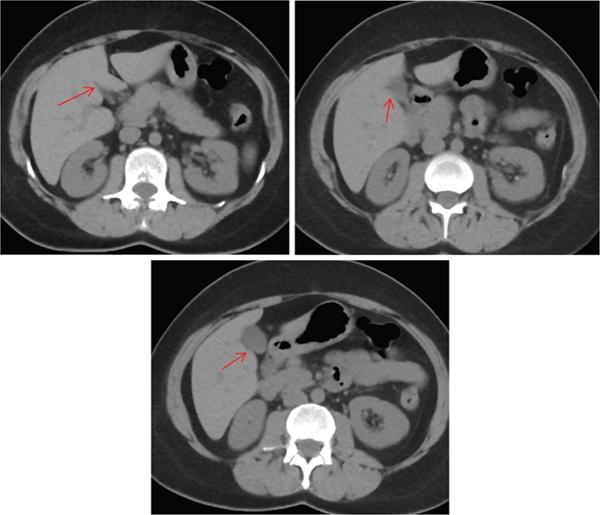

Ritu K. Kashikar, Shrinivas B. Desai Imaging is the mainstay of noninvasive diagnosis of the spectrum of abdominal pathologies or proving absence off thereof. Knowledge of normal anatomy and important normal variants is thus essential for the radiologist in order to avoid misinterpretation or erroneous diagnosis. This chapter highlights the normal anatomy of the hepatobiliary systems including the blood vessel and draining ducts and discusses relevant anatomical variants which may have important clinic implications. The liver is the largest abdominal organ, occupying the right upper abdominal quadrant and is in close approximation with the diaphragm, stomach and the gallbladder. It is largely covered by the costal cartilages. The liver is encapsulated by Glisson’s capsule which is a dense layer of connective tissue. It is covered by peritoneum, except in the regions of gallbladder fossa, fossa for inferior vena cava (IVC), and the bare area. The bare area is the posterocranial aspect of the liver, adjacent to the dorsal body wall, which is not covered by peritoneum. The liver has two surfaces, the convex diaphragmatic surface and a concave visceral surface. The slit in the hepatic hilum is called the porta hepatis and is penetrated by the right and left hepatic ducts (LHDs), hepatic artery and portal vein (PV). The distal portion of the lesser omentum is called the hepatoduodenal ligament and contains the common bile duct (CBD), hepatic artery, PV, nerves of liver and lymphatics. The liver has dual blood supply with hepatic artery providing 25% of hepatic blood and rest by portal vein (Fig. 9.2.1). Five ligaments connect the liver to the undersurface of the diaphragm. These include the falciform, the coronary and two lateral ligaments, all of which are peritoneal folds. The fifth ligament is a fibrous cord-like structure and represents the obliterated umbilical vein. The peritoneum invaginates into the liver parenchyma leading to formation of fissures. There are four normal fissures: fissures for the ligamentum teres, ligamentum venosum and gallbladder and the transverse fissure (Fig. 9.2.2). The liver is organized into microscopic functional units called lobules or acini. A central terminal hepatic venule surrounded by four to six terminal portal triads form a polygonal unit called the hepatic lobule. The terminal portal triad branches line the periphery of the unit. Between the terminal portal triads and the central hepatic venule the hepatocytes are arranged in one cell thick plates, surrounded by sinusoids. The blood flows from the terminal portal triad through sinusoids into terminal hepatic venule. Bile formed within the hepatocytes empties into terminal canaliculi which coalesce into the bile ducts (Fig. 9.2.3). This structure of the functional hepatic unit forms the basis of various functions of the liver. The normal relations of the liver are: The liver can be divided into right, left and caudate lobes. The right and left lobes are separated by the interlobular fissure and is oriented along a line passing through the gallbladder fossa inferiorly and the middle hepatic vein (MHV) superiorly (Fig. 9.2.4). This plane runs from the left of the IVC to the left of the gallbladder fossa and is a called the Cantlie’s line. Use of standardized, segmental anatomy is imperative because it facilitates communication and treatment planning. The segmental anatomy of liver is primarily based on vascular anatomy. The right lobe is divided into anterior and posterior sectors by of the right hepatic vein (RHV). The left lobe is divided into medial and lateraI sectors by an oblique plane connecting the left hepatic vein (LHV) and the falciform ligament. The liver is divided into upper and lower segments at the level of main portal vein (MPV) bifurcation (Fig. 9.2.5). Various systems are used in classification of liver anatomy. These are discussed in Table 9.2.1. The Couinaud’s system is the most commonly used and divides eight sections/segments which are discussed in details below (Table 9.2.2). 1. Segment 1 – Caudate lobe Bounded anteriorly and medially by the fissure for ligamentum venosum (Fig. 9.2.6). 2. Segment 2: Superior segment of the left lateral sector/section Bounded medially by falciform ligament and inferiorly by plane of MPV, also known as the posterior lateral sector (Bismuth, FCAT) (Fig. 9.2.7). 3. Segment 3: Inferior segment of left lateral sector/section Bounded medially by the falciform ligament and superiorly by the plane of the MPV bifurcation, also referred to as lateral anterior sector (Bismuth, FCAT) (Fig. 9.2.8). 4. Segment 4: Left medial sector/section Bounded laterally by falciform ligament and medially by Cantlie’s line (Fig. 9.2.9). 5. Segment 5: Inferior segment of the right anterior sector/section Bounded anteriorly by the gallbladder fossa and posteriorly by the plane of the RHV, superiorly bounded by the plane of MPV bifurcation (Fig. 9.2.10). 6. Segment 6: Inferior segment of the right posterior sector/section Bounded anteriorly by plane of the RHP and superiorly by the plane of the MPV bifurcation (Fig. 9.2.11). 7. Segment 7: Superior segment of the right posterior sector/section Bounded anteriorly by the plane of the RHV and inferiorly by the plane of the MPV bifurcation (Fig. 9.2.12). 8. Segment 8: Superior segment of the right anterior sector/section Bounded anteriorly by the plane of the gallbladder fossa and MHV, posteriorly bounded by the plane of the RHV and inferiorly by the plane of the MPV bifurcation (Fig. 9.2.13). Owing to its broad area of contact with the anterior abdominal wall, the liver is an ideal organ for evaluation with sonography. Ultrasound is commonly used for evaluation of size of the liver. On longitudinal scans obtained through the midhepatic line, if the liver measures 13 cm or less, it is normal in 93% of individuals (Fig. 9.2.14). The size of liver in various planes is discussed in chapter on normograms. When the area of contact between the liver and the anterior border of the right kidney, exceeds below two thirds of the kidney, the liver is considered as enlarged. The normal liver is homogeneous with fine echoes and appears evenly bright. The hepatic veins, PV and fissures interrupt the homogeneity of the liver parenchyma (Fig. 9.2.15). The parenchymal echogenicity may vary depending on the equipment, transducer and gain settings and should be judged by comparison with internal references like right renal cortex, body of the pancreas and PV walls. When compared with the adjacent normal right renal cortex the liver normally appears hyperechoic or isoechoic. The pancreas in a young individual is hypoechoic compared to the liver, and isoechoic in middle aged adults. As age progresses and fatty infiltration of the pancreas occurs, the pancreas appears hyperechoic to the liver. The liver is hypoechoic to the spleen. The normal liver reveals a density of 55–65 HU on nonenhanced scan and should appear homogenous with the exception of hypodensity in the regions of vessels and fissures. The liver parenchymal enhancement is minimal the arterial phase, with increase in density by only approximately 10 HU. This phase is usually to access vascular anatomy and to detect neovascular enhancing lesion like HCC, metastasis. Considering the fact that 75% of heptic venous supply is from the PV, the normal hepatic parenchyma shows maximum enhancement in the portal venous phase. During the venous/delayed phase the hepatic attenuation starts falling (Fig. 9.2.16). The hepatic fissures appear as linear fat containing structures. All the four fissures are well identifies on CT (Figs. 9.2.17–9.2.20). Normal liver should demonstrate uniform T1 signal similar or isointense to the paraspinal muscles and slightly hyper intense to the spleen. No signal drop should be seen on in or opposite phase. On T2W1 images liver appears slightly hyperintense to paraspinal muscles, isointense to pancreas and hypointense to spleen (Fig. 9.2.21). Following administration of extracellular contrast agents the normal liver parenchyma enhances on PV phase similar to that seen on CT. The arterial phase is preserved to determining vascular anatomy, variants and tumoural enhancement. Gadoxetic acid (Eovist) and gadobenate dimeglumine (MultiHance) are hepatobiliary agents showing excretion by the liver. In the case of gadoxetic acid, hepatic excretion is ~50%, which allows imaging in the hepatobiliary phase at ~20 minutes following injection. Gadobenate has only 3%–5% biliary excretion with hepatobiliary phase at approximately 40 minutes (Fig. 9.2.22). This property makes these agents useful in detection of nonhepatocyte containing lesions which appear hypointense to background liver on hepatobiliary phase. Hepatic anatomic variants are relatively common and represent normal interindividual variation of liver morphology. Normal Anatomic Variants Anatomic anomalies Accessory and pseudofissures may be seen in the liver. True accessory fissures result from infolding of the peritoneum usually along the undersurface of the liver and are rare. The inferior accessory fissure is the commonest accessory fissure and divides the posterior segment of the right hepatic lobe into lateral and medial portions. Diaphragmatic slips may cause indentation over the liver surface and are not commonly seen on imaging (Fig. 9.2.23). Leftward extension of the lateral segment of the left hepatic lobe appearing as a crescentic density that wraps around the spleen is referred to as sliver of liver. The left lobe of the liver may exhibit various forms: leaf like; spatular; truncated pyramid/wedge shaped; and a bifid appearance (Fig. 9.2.24). Elongated left lobe may be mimic splenomegaly, perisplenic hypoechoic collections or less commonly tumours. Imaging clues to diagnosis are establishing contiguity with liver and visualization of parenchymal vessels coursing through. The portion of the liver that extends medially from the right lobe between the IVC and fissure for ligamentum venosum is called the caudate lobe. The caudate lobe is divided inferiorly into a lateral caudate process and a medial papillary process. The medial papillary process projects medially towards the pancreatic head and has applied importance (Fig. 9.2.25). Riedel’s lobe is a tongue-like projection from the anterior aspect of the right lobe and the most common accessory lobe of the liver. It is seen most frequently in asthenic women. The reported prevalence of RL, ranges from 3.3% to 14.5% and the prevalence is higher in women than in men. It can be 20 cm or more in length and may extend up to the iliac fossa. It is usually asymptomatic and is discovered incidentally (Fig. 9.2.26). Accessory liver lobes are defined as a supernumerary lobe of normal hepatic parenchyma in continuity with the liver. This is a rare entity and usually occurs as a result of congenital ectopic hepatic tissue, although rarely may occur as a result of trauma or surgery. Various systems are proposed for classification of ALL. Another method of classification has been proposed based on biliary drainage and presence or absence of capsule. Accessory lobes can be readily diagnosed and characterized on CT or magnetic resonance imaging (MRI) done for related or unrelated conditions. CT shows the lesion as a soft–tissue density mass attached to the liver and isodense to the organ. The portal/hepatic venous branches can be seen coursing through it, in contiguity with the liver (Fig. 9.2.27). The coeliac axis trifurcates into common hepatic, splenic and left gastric arteries at the level of T12–L1. The common hepatic artery becomes the proper hepatic artery after origin of the gastro-duodenal artery. The hepatic artery proper ascends anterior to the PV and medial to the CBD and divides in to right and left hepatic artery (LHA). Occasionally the middle hepatic (segment 4) artery arises from hepatic artery proper. The hepatic artery appears as a tubular hypoechoic structure and shows antegrade flow on Doppler (Fig. 9.2.28). Normally the resistive index is low ranging between 0.55 and 0.7. The hepatic artery, its anatomy, branches, course, calibre are best evaluated on arterial phase of dynamic CT (Fig. 9.2.29). This is also the preferred modality prior to hepatobiliary surgical planning. Contrast-enhanced MRI also shows the above details but spatial resolution is lower. Road map of the arterial vascularity of the donor and recipient is a prerequisite for transplant surgery and complex hepatobiliary surgery. Detailed hepatic arterial anatomy and its variations have its significance in liver surgeries and interventional hepatic procedures, relative to the hepatic lobe involved. A classification method was described by Michel et al. in 1955, and is discussed in Table 9.2.3 (Fig. 9.2.30). I: standard anatomy ~60% (range 55%–61%) II: replaced LHA ∼7.5% (range 3%–10%) III: replaced RHA ~10% (range 8%–11 %) IV: replaced RHA and LHA ~1% V: accessory LHA from LGA ~10% (range 8%–11%) VI: accessory RHA from SMA ~5% (range 1.5%–7%) VII: accessory RHA and LHA ~1% VIII: accessory RHA and LHA and replaced LHA or RHA ~2.5% IX: CHA replaced to SMA ~3% (range 2%–4.5%) X: CHA replaced to LGA ~0.5% Other unclassified variants are: The two most common variants are the replaced right hepatic artery (RHA) arising from the SMA (Fig. 9.2.31) and replaced LHA arising from the left gastric artery (Figs. 9.2.32–9.2.34). Segment 4 artery – Middle hepatic artery (MHA) The middle hepatic artery usually arises from the LHA, it may, however, arise from the RHA (Fig. 9.2.35). The knowledge regarding origin of MHA is imperative in transplant surgery. The MHA can arise from RHA in Patients with replaced LHA. In patients with replaced RHA, the MHA arises from LHA (Fig. 9.2.36). Because of the considerable variability of hepatic arterial anatomy, assessment of this anatomy is crucial in the preoperative evaluation of potential living liver donors. Relevance of donor and recipient arterial anatomy is discussed in details in chapter on liver transplant. The relationship between the arterial variant and tumour is important to establish prior to major surgeries. Injuries to aberrant hepatic vessels and secondary ischaemic biliary strictures can be avoided. A replaced RHA has a more posterior course and long length. This variant may be advantageous in patients undergoing right lobar resection. However, there is greater propensity of involvement of replaced RHA by pancreatic head. The radiologist must be vigilant in reporting this variant (Fig. 9.2.37). Accessory RHA can, however, be sacrificed even if encased by neoplasm. An accessory LHA needs to be ligated separately in surgeries where blood supply in the porta hepatis is occluded. Replaced LHA from LGA maybe injured in case of surgeries at the level of hiatus. Hence this variant should be informed to surgeon in patients undergoing gastric surgeries. Preoperative mapping of the hepatic arterial anatomy prior to placement of intraarterial chemotherapy pumps is essential because it helps in deciding whether the candidate is suitable for the procedure and also if technical modifications are needed. The intraarterial infusion pump should be placed in the dominant hepatic artery as proximal as possible, but beyond GDA origin. Inpatients with standard anatomy, the pump is usually placed in the hepatic artery prior just after GDA origin. The location of pump can be modified in patients with variant anatomy, based on origin of GDA and dominant hepatic vessel. The PV is the main vessel in the portal venous system and drains blood from the gastrointestinal tract and spleen to the liver.